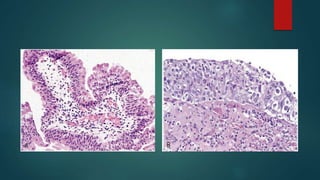

BARRETT ESOPHAGUS:

 Complication of chronic GERD

 Replacement of esophageal squamous

mucosa by metaplastic columnar

epithelium with goblet cells

 Risk of esophageal adenocarcinoma.

HP:

Abundant metaplastic goblet cells, atypical mitosis,

nuclear hyperchromasia.